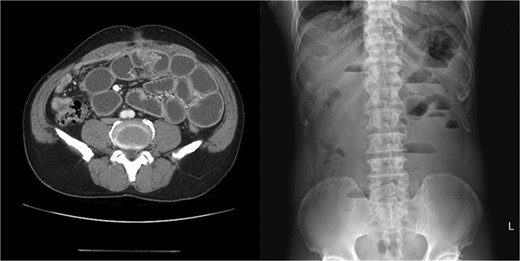

Two weeks later after discharge, he presented to the emergency department with abdominal pain, nausea, vomiting and inability to defecate or pass gas. On examination he was afebrile and his vitals were stable. Only distension of the abdomen was observed. The laboratory examinations were normal, except high CRP level (4.27 mg/dL). Plain abdominal X-rays showed air–fluid levels and abdominal CT showed adhesions at the periumbilical area with dilated small bowel (Fig. 1). He was initially managed conservatively with bowel rest, nasogastric decompression and nutritional support.

Abdomen CT and X-ray showed adhesions at the periumbilical area with dilated small bowel.